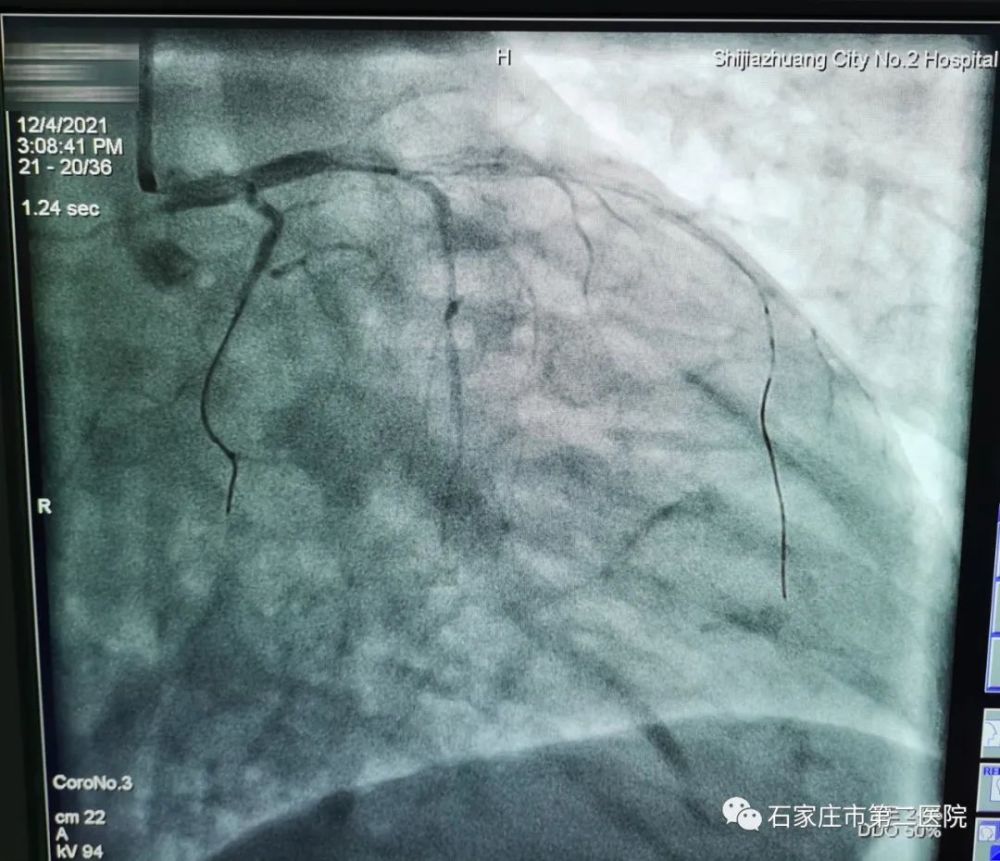

时间紧迫,必须尽快疏通这条生命主干道,为患者心脏正常运转创造条件。李秀彩当即决定,进行冠脉内溶栓治疗。在导管室医护人员的协助下,经过系列高度紧张、精密的溶栓治疗和手术操作,终于再次血管疏通,成功植入支架。术后血流恢复,病人胸痛缓解,血压也明显好转了。

右图:手术后,血流恢复,血管显现